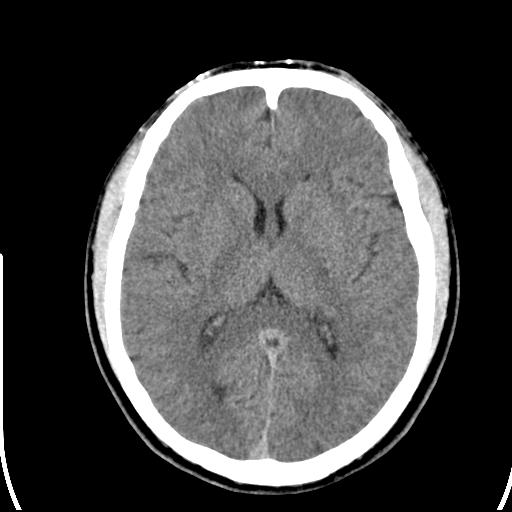

标题: CT25435:头皮下高密度影???

头皮下高密度结节影???临床上在老年男性比较常见。大家看看是什么?成因是? 本例患者,男性,51岁。外伤来诊。无染发史及发根植入史。